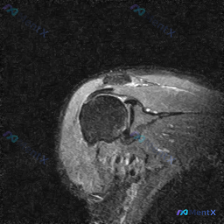

看到一份肩关节MRI的影像分析资料,患者的问题是关于盂唇病变的,但影像报告里提到了几个关键点:冈上肌腱附着处有T2高信号、连续性中断,关节液流入肩峰下间隙;肩峰下-三角肌下滑囊有积液;关节腔也有积液;而盂唇只描述为「形态可辨」。 大家觉得这个病例的核心诊断更可能是什么?是盂唇病变,还是肩袖问题?或者...

最近看到一份肩部MRI-T2序列冠状位的病例资料,原始问题是Labral pathology(盂唇病变)。先放主要的影像描述,大家来分析一下: 影像发现: 1. 冈上肌腱:肱骨大结节止点处连续性中断,断端高信号填充,全层撕裂伴回缩 2. 肩峰下区域:滑囊积液,肩峰前外侧缘锐利,间隙变窄,有撞击征象...

整理了一个挺有代表性的年轻运动员肩痛病例,结合影像和临床分析一下思路。 基本情况 26岁女性,排球运动员,主诉过头动作时肩膀疼痛,并且逐渐无力。初级保健医生做了MRI,转来进一步评估。 关键影像表现(MRI-T2冠状位) 影像上的发现非常明确: 1. 冈上肌腱:连续性明显中断,止点附近T2高信号贯穿...